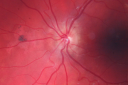

Central Retinal Venous Occlusion with Papilledema, Intraretinal Hemorrhage and Macular Edema824 views